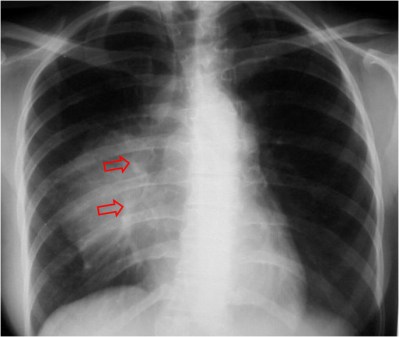

SIGNO DEL HILIO TAPADO u OCULTACIÓN HILIAR

Signo visible en la radiografía posteroanterior de tórax que permite reconocer si una masa es hiliar o mediastínica. Cuando la masa es hiliar está en contacto con la arteria pulmonar y la borra. En cambio, cuando vemos la masa superpuesta a la arteria pulmonar (flechas) sin borrarla, entonces la lesión no es hiliar, sino que se sitúa anterior (más comúnmente) o posterior al hilio. La imagen corresponde a una paciente con un linfoma, es decir,una masa mediastínica anterior.